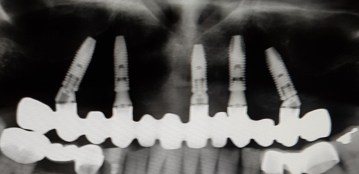

Felső fogatlan állcsont korszerű ellátása: felső teljes fogatlanság kezelése 6 implantátumon rögzített fix híddal. Multi unit tengelykorrekciós fejek, csavarosan rögzített híd.

Implantátum: Nobel Biocare.

Hídpótlás anyaga: cirkónium vázra égetett porcelán.

A választott fogszín: A1.

A protetikai munka elkészülésének ideje: 8 munkanap.